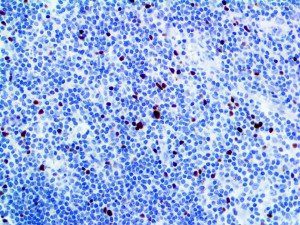

It is the ICU physician who is most likely to witness one of the deadliest manifestations of the abnormal immunological response, the cytokine storm syndrome (CSS). This response is also referred to by some as the cytokine release syndrome (CRS). CSS is characterized by continuous activation and expansion of macrophage and lymphocyte populations, which secrete large amounts of cytokines, causing the cytokine storm. This massive cytokine release is akin to hemophagocytic lymphohistiocytosis (HLH) disease, a syndrome characterized by initial unchecked and persistent activation of cytotoxic T lymphocytes and NK cells.

Clinical and laboratory manifestations of HLH include fever, enlarged liver and/or spleen, neurologic dysfunction, coagulopathy, liver dysfunction, cytopenias (i.e., low levels of erythrocytes, leukocytes, and/or platelets), hypertriglyceridemia, hyperferritinemia, hemophagocytosis, and eventually diminished NK cell activity as the immune system becomes progressively paralyzed. HLH can be familial (primary HLH) or secondary to another disease process (sHLH), such as rheumatic disease, in which it is referred to as macrophage activation syndrome (MAS, characterized by elevated ferritin).